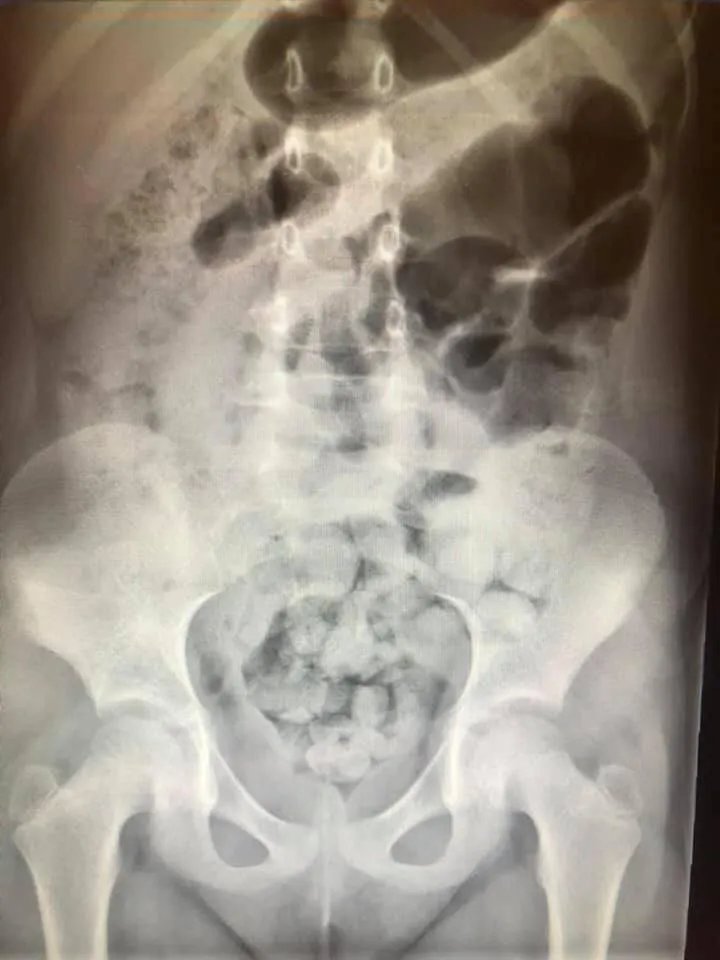

在急診聽到這種話,我們會默默開一張腹部X光,通常照出來就是像圖片一樣滿肚子大便。

💩大出來的根本是冰山一角...